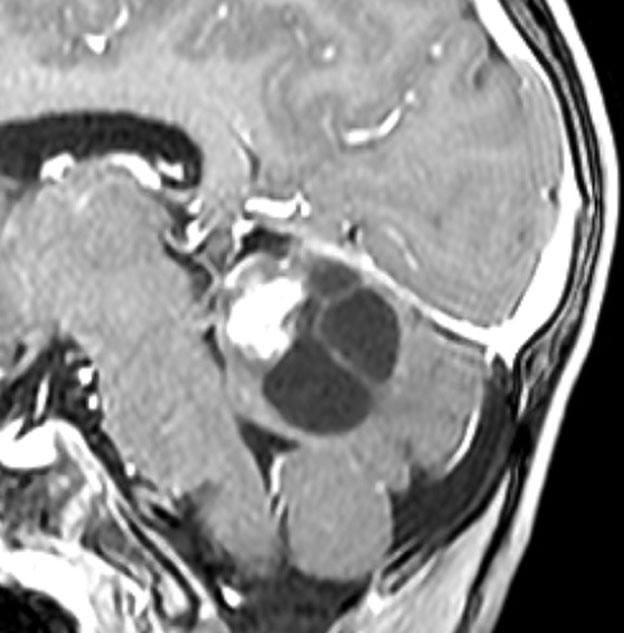

4歳発症の大きなもの

これも小脳中部上端から発生したもので,中脳水道が開いています。OTAで摘出しなければ小脳中部に大きな損傷を与えるものですから,後頭下開頭をしてはなりません。術後10年ほど経ちますが再発はなくてダンスをしてます。